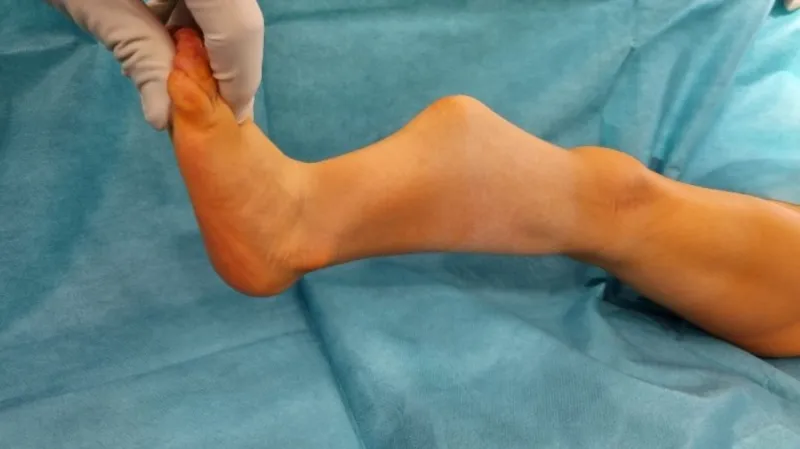

S tímto vzácným onemocněním přišli na svět i dnes čtyřletý Mikuláš a tříletá Antonie. Obě děti mají za sebou operaci v brněnské fakultní nemocnici. Díky nové metodě a speciálnímu implantátu, který s pacientem roste, mohou chodit a běhat téměř jako ostatní.

„Zákrok trvá okolo pěti hodin, kdy se zavede kovový implantát do dřeňové dutiny kosti. Ten je v horní části bérce fixován závitem, v dolní drátkem. Tím, že je kovový implantát fixován nad a pod růstovými zónami bérce, kost může růst a implantát víceméně roste s pacientem,“ vysvětlil Karel Urbášek, vedoucí ortoped Kliniky dětské chirurgie, ortopedie a traumatologie FN Brno.

Pro úspěšné spojení holenní a lýtkové kosti je nutné odebrat pacientovi veškerou kost z vnitřku jedné poloviny pánve, ta se v průběhu šesti až dvanácti týdnů po operaci plně obnoví. Metoda umožňuje pacienta operovat už v 18 měsících, dříve používané postupy umožňovaly operaci až ve třech nebo čtyřech letech. Dítě přitom až do operace nemůže samo chodit.